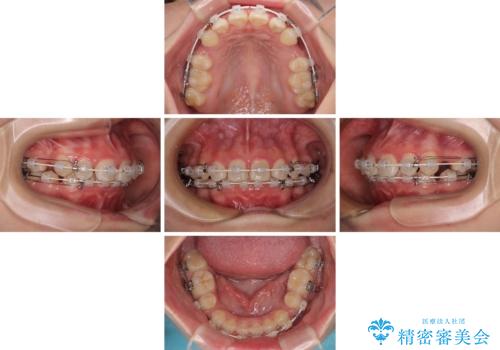

- 矯正装置

- 審美装置

- 治療期間

- 2年9ヶ月

- 治療回数

- 30回以上

- 下唇の上に乗っかってしまうくらい前歯が飛び出していることを気にして来院された患者様です。

唇を閉じようとするとオトガイ部に力が入ってしまい、うまく閉じることができない状態であったため、上下左右の第一小臼歯4本を抜歯して、ワイヤー装置にて矯正治療を行うこととしました。

飛び出した前歯はしっかりと引っ込み、横顔の印象が大きく変化しました。